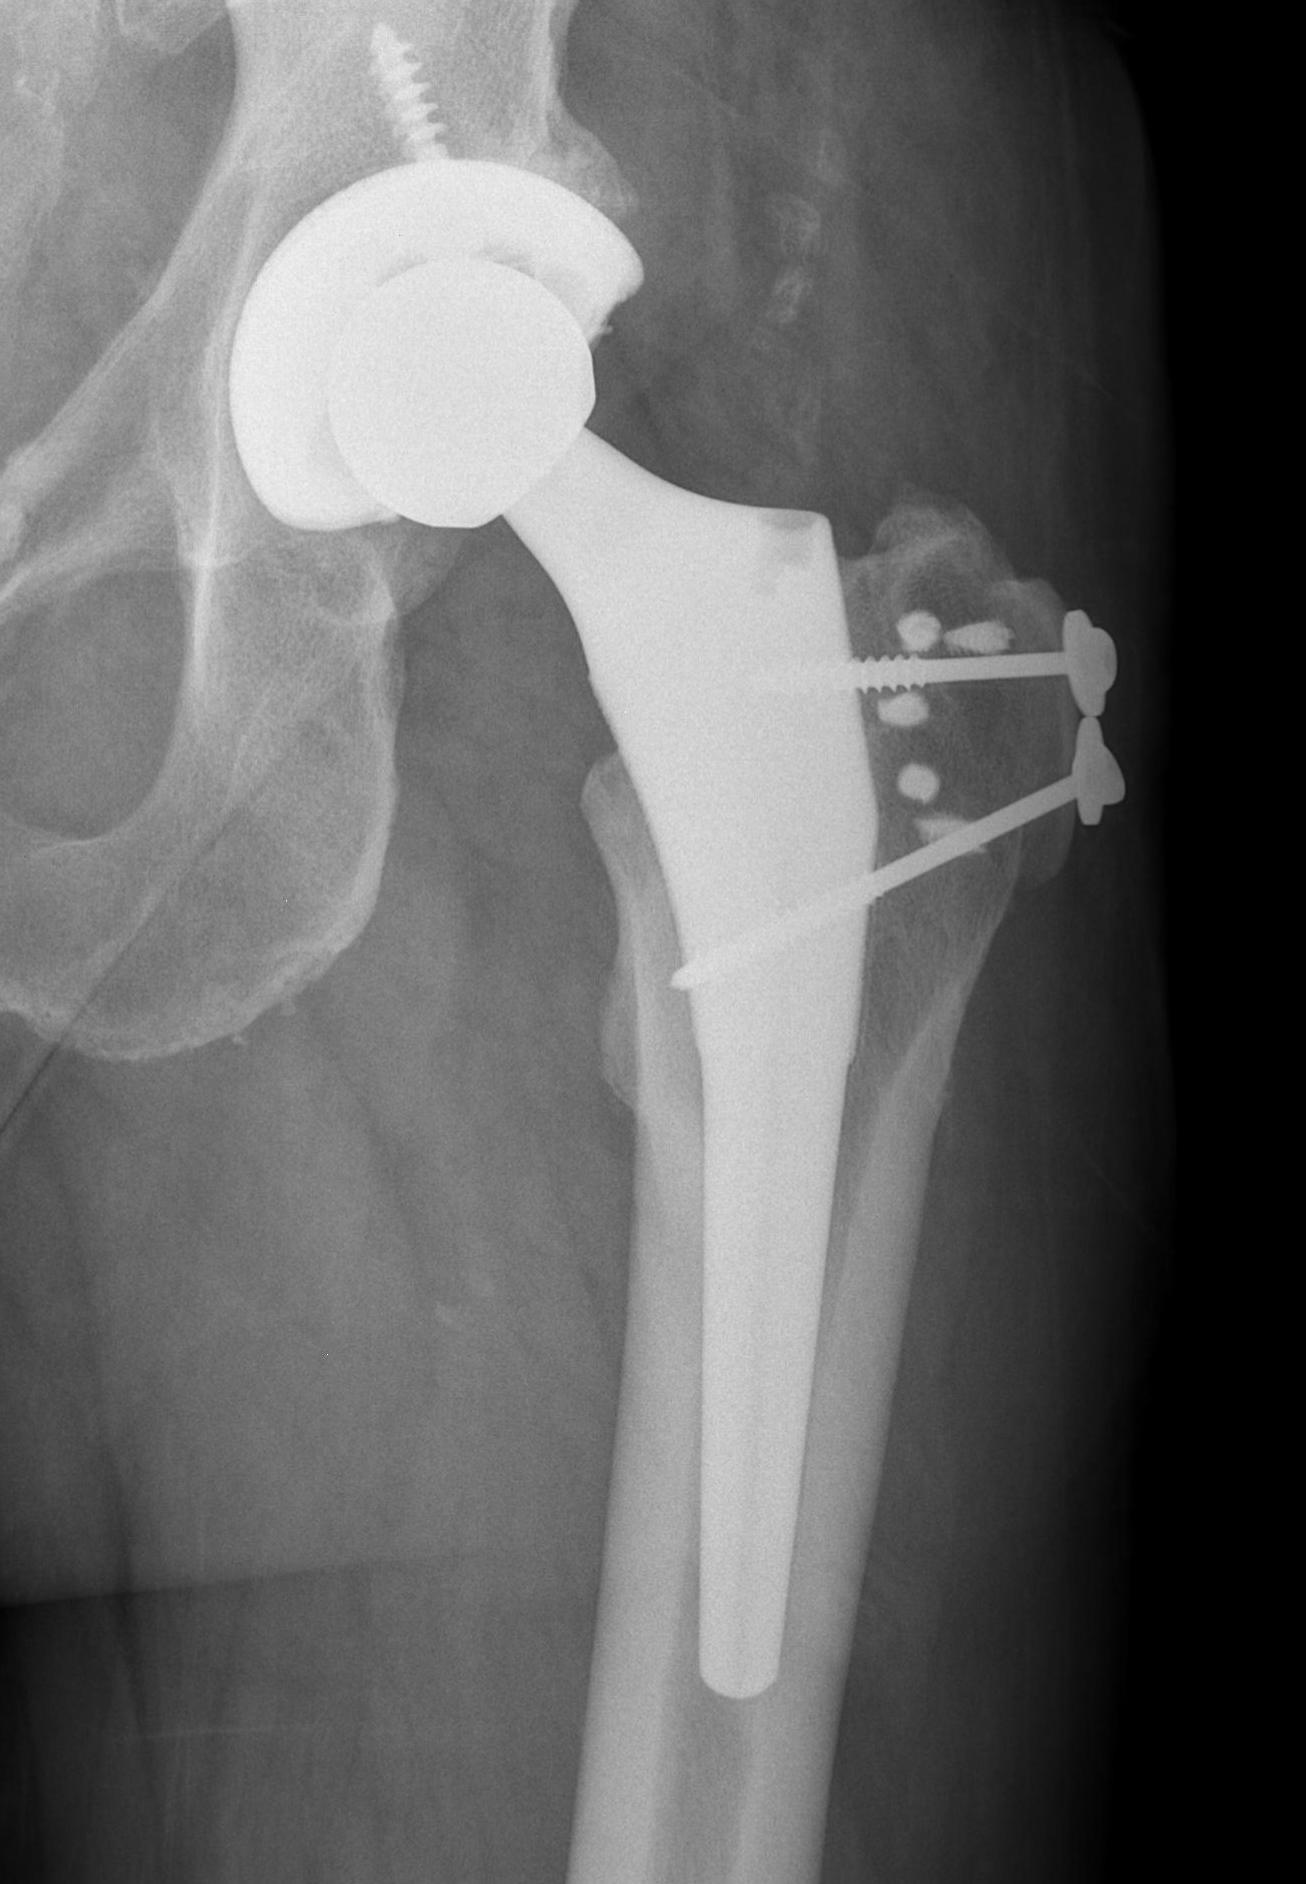

Post Total Hip Arthoplasty

Miozzari et al J Arthroplasty 2010

- late abductor repair in 12 patients following transgluteal THA

- 25% failure rate